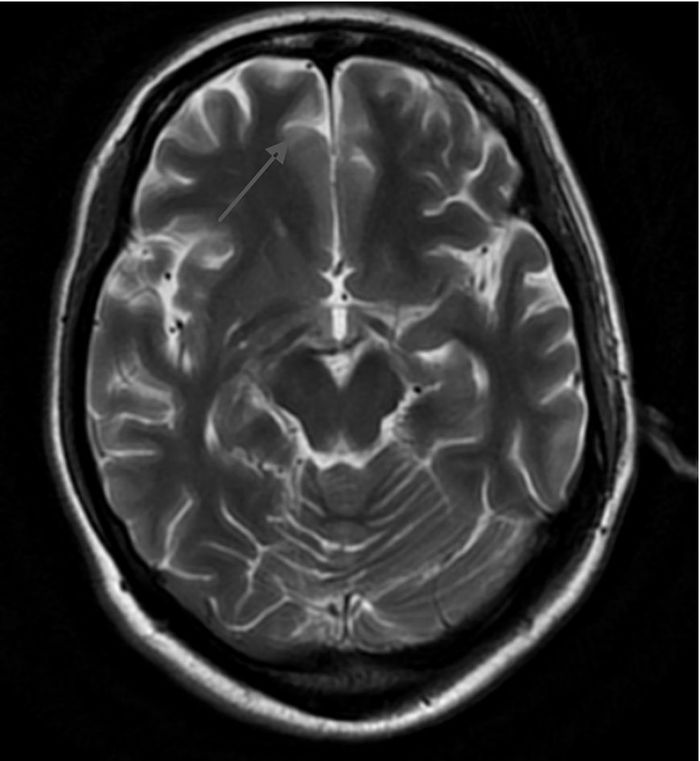

1 资料与方法患者女性,39岁,主因“复视1周,行走不稳4 d,意识障碍2 d”于2015年10月20日就诊北京大学人民医院急诊科。患者1周前出现复视,伴视物模糊、头晕,无头痛、恶心、呕吐。4 d前出现行走不稳,需家人搀扶,伴乏力。2 d前间断嗜睡,且意识障碍逐渐加重,后因呼之无反应,就诊当地医院行头颅CT示“脑桥可疑低密度灶”。既往:“慢性胰腺炎、慢性胆囊炎”3个月,进食差。否认药敏史。入院查体:T 37.8 ℃,HR 118次/min,RR 25次/min,BP 95/65 mmHg (1 mmHg=0.133 kPa),SpO2 90%。昏迷。双侧瞳孔等大等圆,直径3 mm,对光反射消失。双肺呼吸音粗,未闻及干湿性啰音。心率118次/min,律齐,心音较低,各瓣膜听诊区未闻及病理性杂音。腹软,肝脾肋下未触及。双下肢肌张力减低。病理征阴性。入我科后完善相关检查:血常规:WBC 6.28×109 L-1、Hb 104 g/L、PLT 279×109 L-1;生化全项:ALT 146 U/L、AST 81 U/L、ALB 40 g/L、GLU 6.87 mmol/L、TBIL 34.2 μmol/L、DBIL 15.3 μmol/L、Na+ 138 mmol/L、K+ 4.0 mmol/L、CRE 78 μmol/L;血气分析:pH 7.37,PaO2 168 mmHg (FiO2 29%),PaCO2 37 mmHg,SaO2 98%,Lac 2.7 mmol/L;头颅CT未见明显异常。初步诊断为意识障碍待查、肝功能损伤待查,予改善循环、营养神经、营养支持、护肝等治疗。考虑到患者院外饮食不佳近3个月,存在WE可能,予维生素B1 100 mg每日2次肌注。次日患者出现低氧血症,SpO2 78%~85%;血气分析:pH 7.36,PaO2 88 mmHg (FiO2 41%),PaCO2 30 mmHg,SaO2 83%,Lac 3.6 mmol/L;予气管插管接呼吸机辅助通气。10月28日脱机、拔除气管插管,予无创呼吸机序贯治疗。10月29日行头颅MRI示“双侧额叶皮层(图 1)、双侧丘脑、下丘脑、第三脑室、中脑导水管周围脑实质(图 2、图 3)异常信号影,符合Wernicke's脑病表现”,为进一步治疗收住院。入院后继续予营养神经、改善脑部血液循环、维生素B1 100 mg每日2次肌注等治疗。患者神志逐步恢复正常,可正常交流及缓慢行走,但表情淡漠、记忆力下降,复查肝功能正常,于2015年12月8日离院,门诊随访。

| 图 1 T2WI双侧额叶皮层异常信号 |